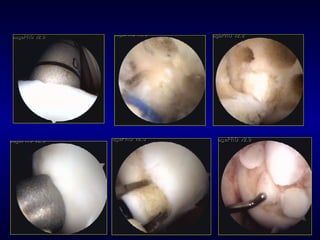

F.U.: 6 MESI

Innesto singolo da 8 mm a 6 mesi

F.U. 6 MESI

F.U.: 8 Mesi

F.U.  8 MESI SITO DI PRELEIVO 8 MESI